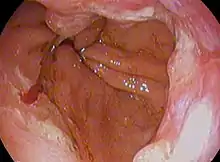

![]() | |

| Endoscopic image of Barrett's esophagus, which is the area of dark reddish-brown mucosa at the base of the esophagus. (Biopsies showed intestinal metaplasia.) | |